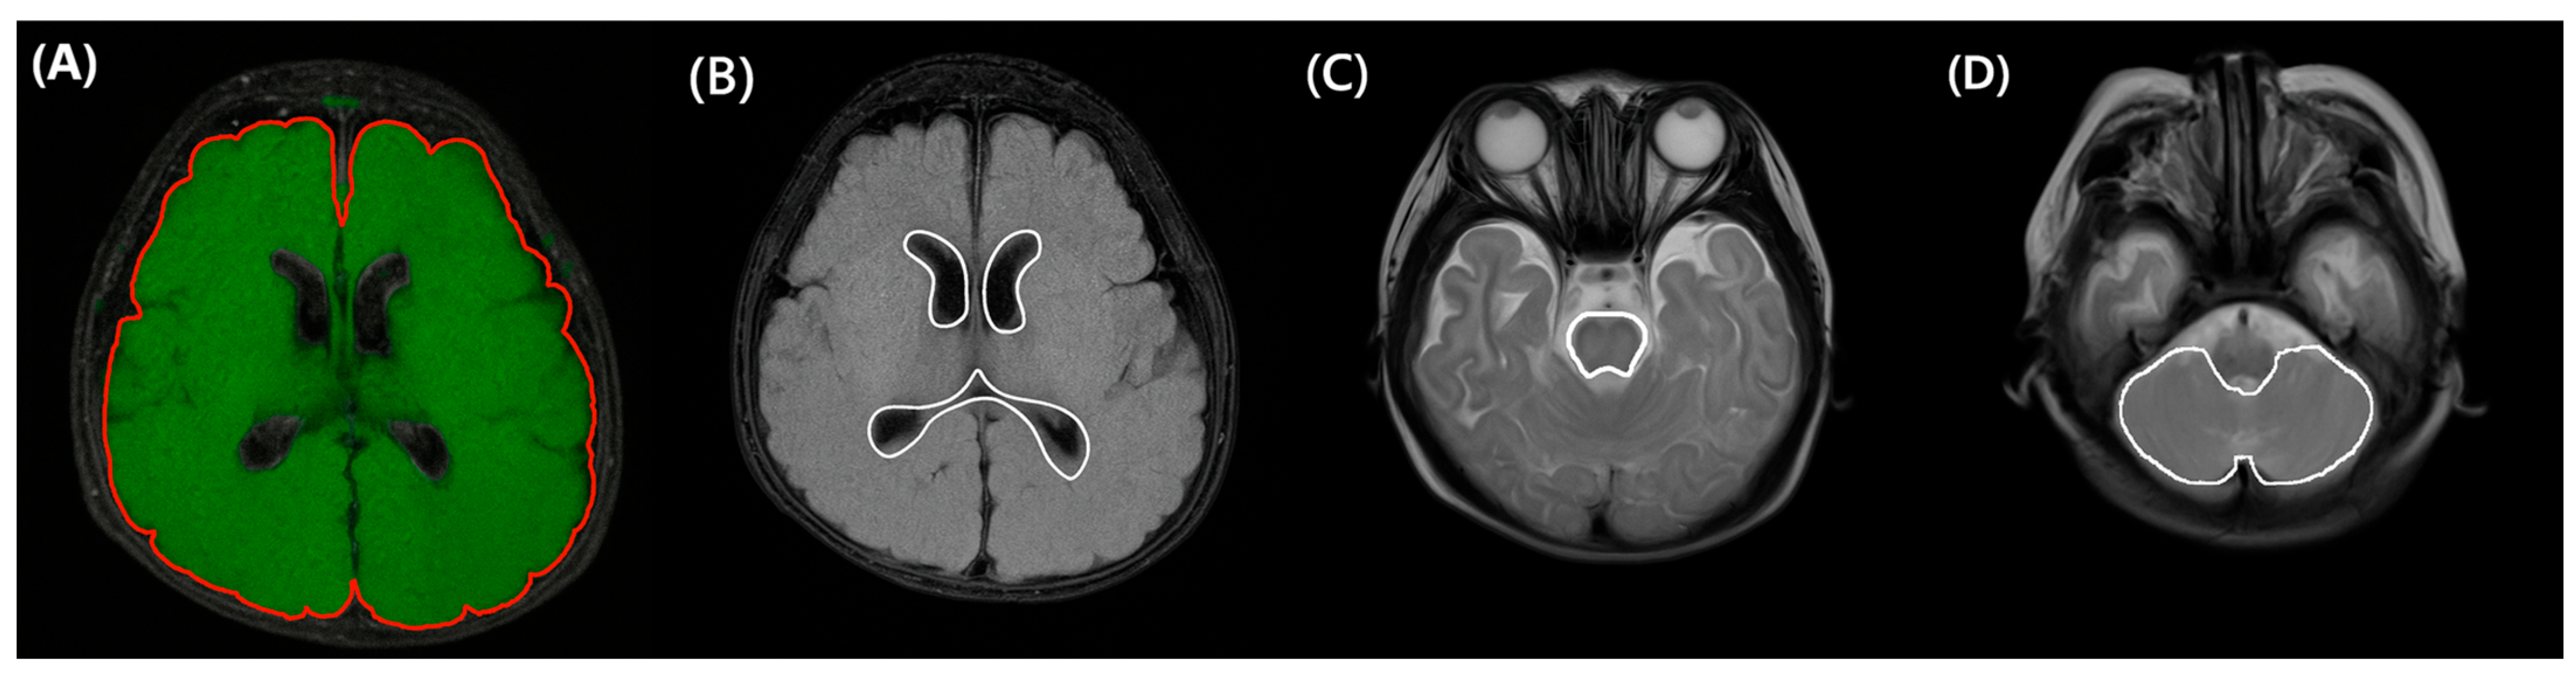

In our center, brain MRI is routinely performed in very preterm or VLBW infants to screen for white matter injuries. According to our protocol, MRI is recommended at TEA. However, if the infant is medically unstable, the scan is delayed. Conversely, if earlier imaging is clinically indicated, MRI may be performed prior to TEA. Minimizing the confounding effect of brain growth, we selected brain MRI scanned between the previously mentioned window period: obtained between 36+0 to 44+6 weeks of PMA. Axial fluid-attenuated-inversion-recovery and T2 MRI images (Figure 2) were annotated by a technician (TE) using a 3D workstation (Aquarius iNtuition, TeraRecon Inc., Durham, NC, USA) program. The results were reviewed and confirmed by a pediatric radiologist (ISA). The evaluators were blinded to the clinical outcomes. Based on these annotations, quantitative assessment (total brain volume, cerebral volume, cerebellar volume, brainstem volume, and ventricular volume) was performed. The segmented structures were reconstructed in 3D to confirm shape accuracy; an example is shown in Figure 3.

Figure 2.

Regional structure marking: Intracranial (A) and ventricle (B) marking was drawn on an axial FLAIR T2 FAT sequence. Brain stem (C) and cerebellar (D) marking was drawn on a T2-Weighted TSE sequence. FLAIR, Fluid-Attenuated Inversion Recovery.